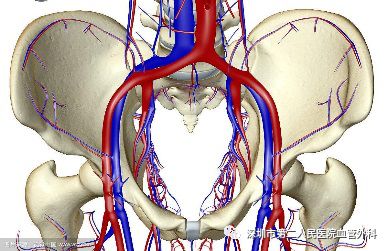

深静脉血栓形成的英文简称叫DVT,多发生于下肢,可发生于髂静脉、股静脉、腘静脉、胫静脉及小腿肌肉静脉丛等各级深静脉(图1)。此病在中老年朋友中并不少见,特别是有血栓形成高危因素的人群中更是多见。那么,静脉血栓因何产生?为什么好发于下肢深静脉?如何发展?有何危害?遇到这种情况,我们又该如何应对呢?

图1 下肢各级深静脉及其与浅静脉的关系

三、血栓为什么好发于下肢深静脉,且多发于左侧

静脉的血流速度远小于动脉,因此,静脉血栓的发病率要远远高于动脉。在静脉系统中,血液回流的主要阻力是血液本身的重量,而下肢处于人体的最低处,向上回流时所需克服的重力就最大,血栓当然就易发。之所以左下肢更多发,是由于左髂静脉前面被右髂动脉跨越、压迫(图4),后面又是坚硬的脊柱,形成一个天然的狭窄,因此,左下肢的血液回流更难些,因此更易发生血栓。

图4 左髂静脉被右髂动脉跨越压迫